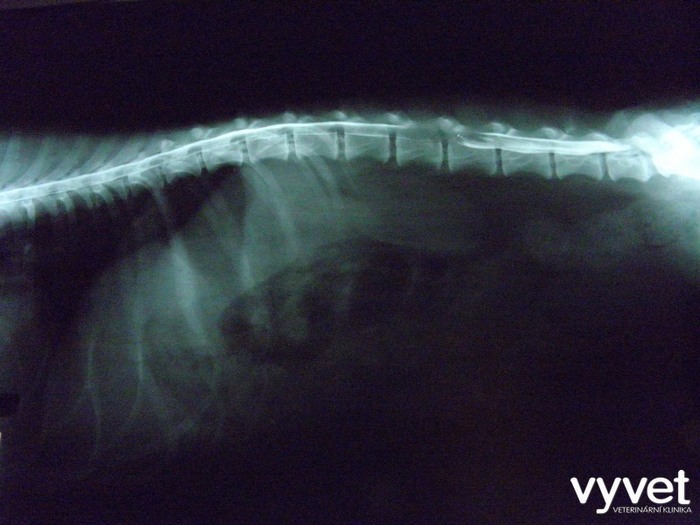

Laterální snímek pacienta s viditelnou kompresí (utlačením) míchy